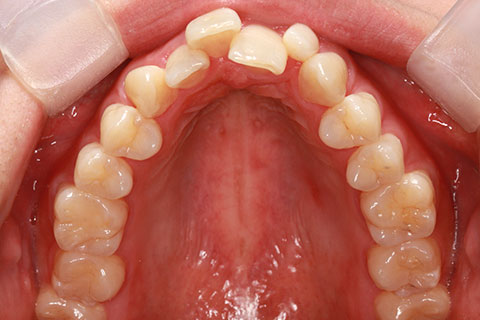

ハーフリンガル矯正3:上の歯のみ舌側矯正で治療(矯正期間24ヶ月)

治療前

治療中(開始直後)

治療中(開始半年後)

治療後

- 年齢・性別

- 25歳女性

- 治療期間

- 2年0ヶ月

- 抜歯

- 上下4番抜歯

- 治療費

- 110万円

- 治療内容

- 施術の副作用(リスク)

- 表側矯正と比較して、力学的な操作性が複雑なため、ボーイングエフェクトを起こしやすい。